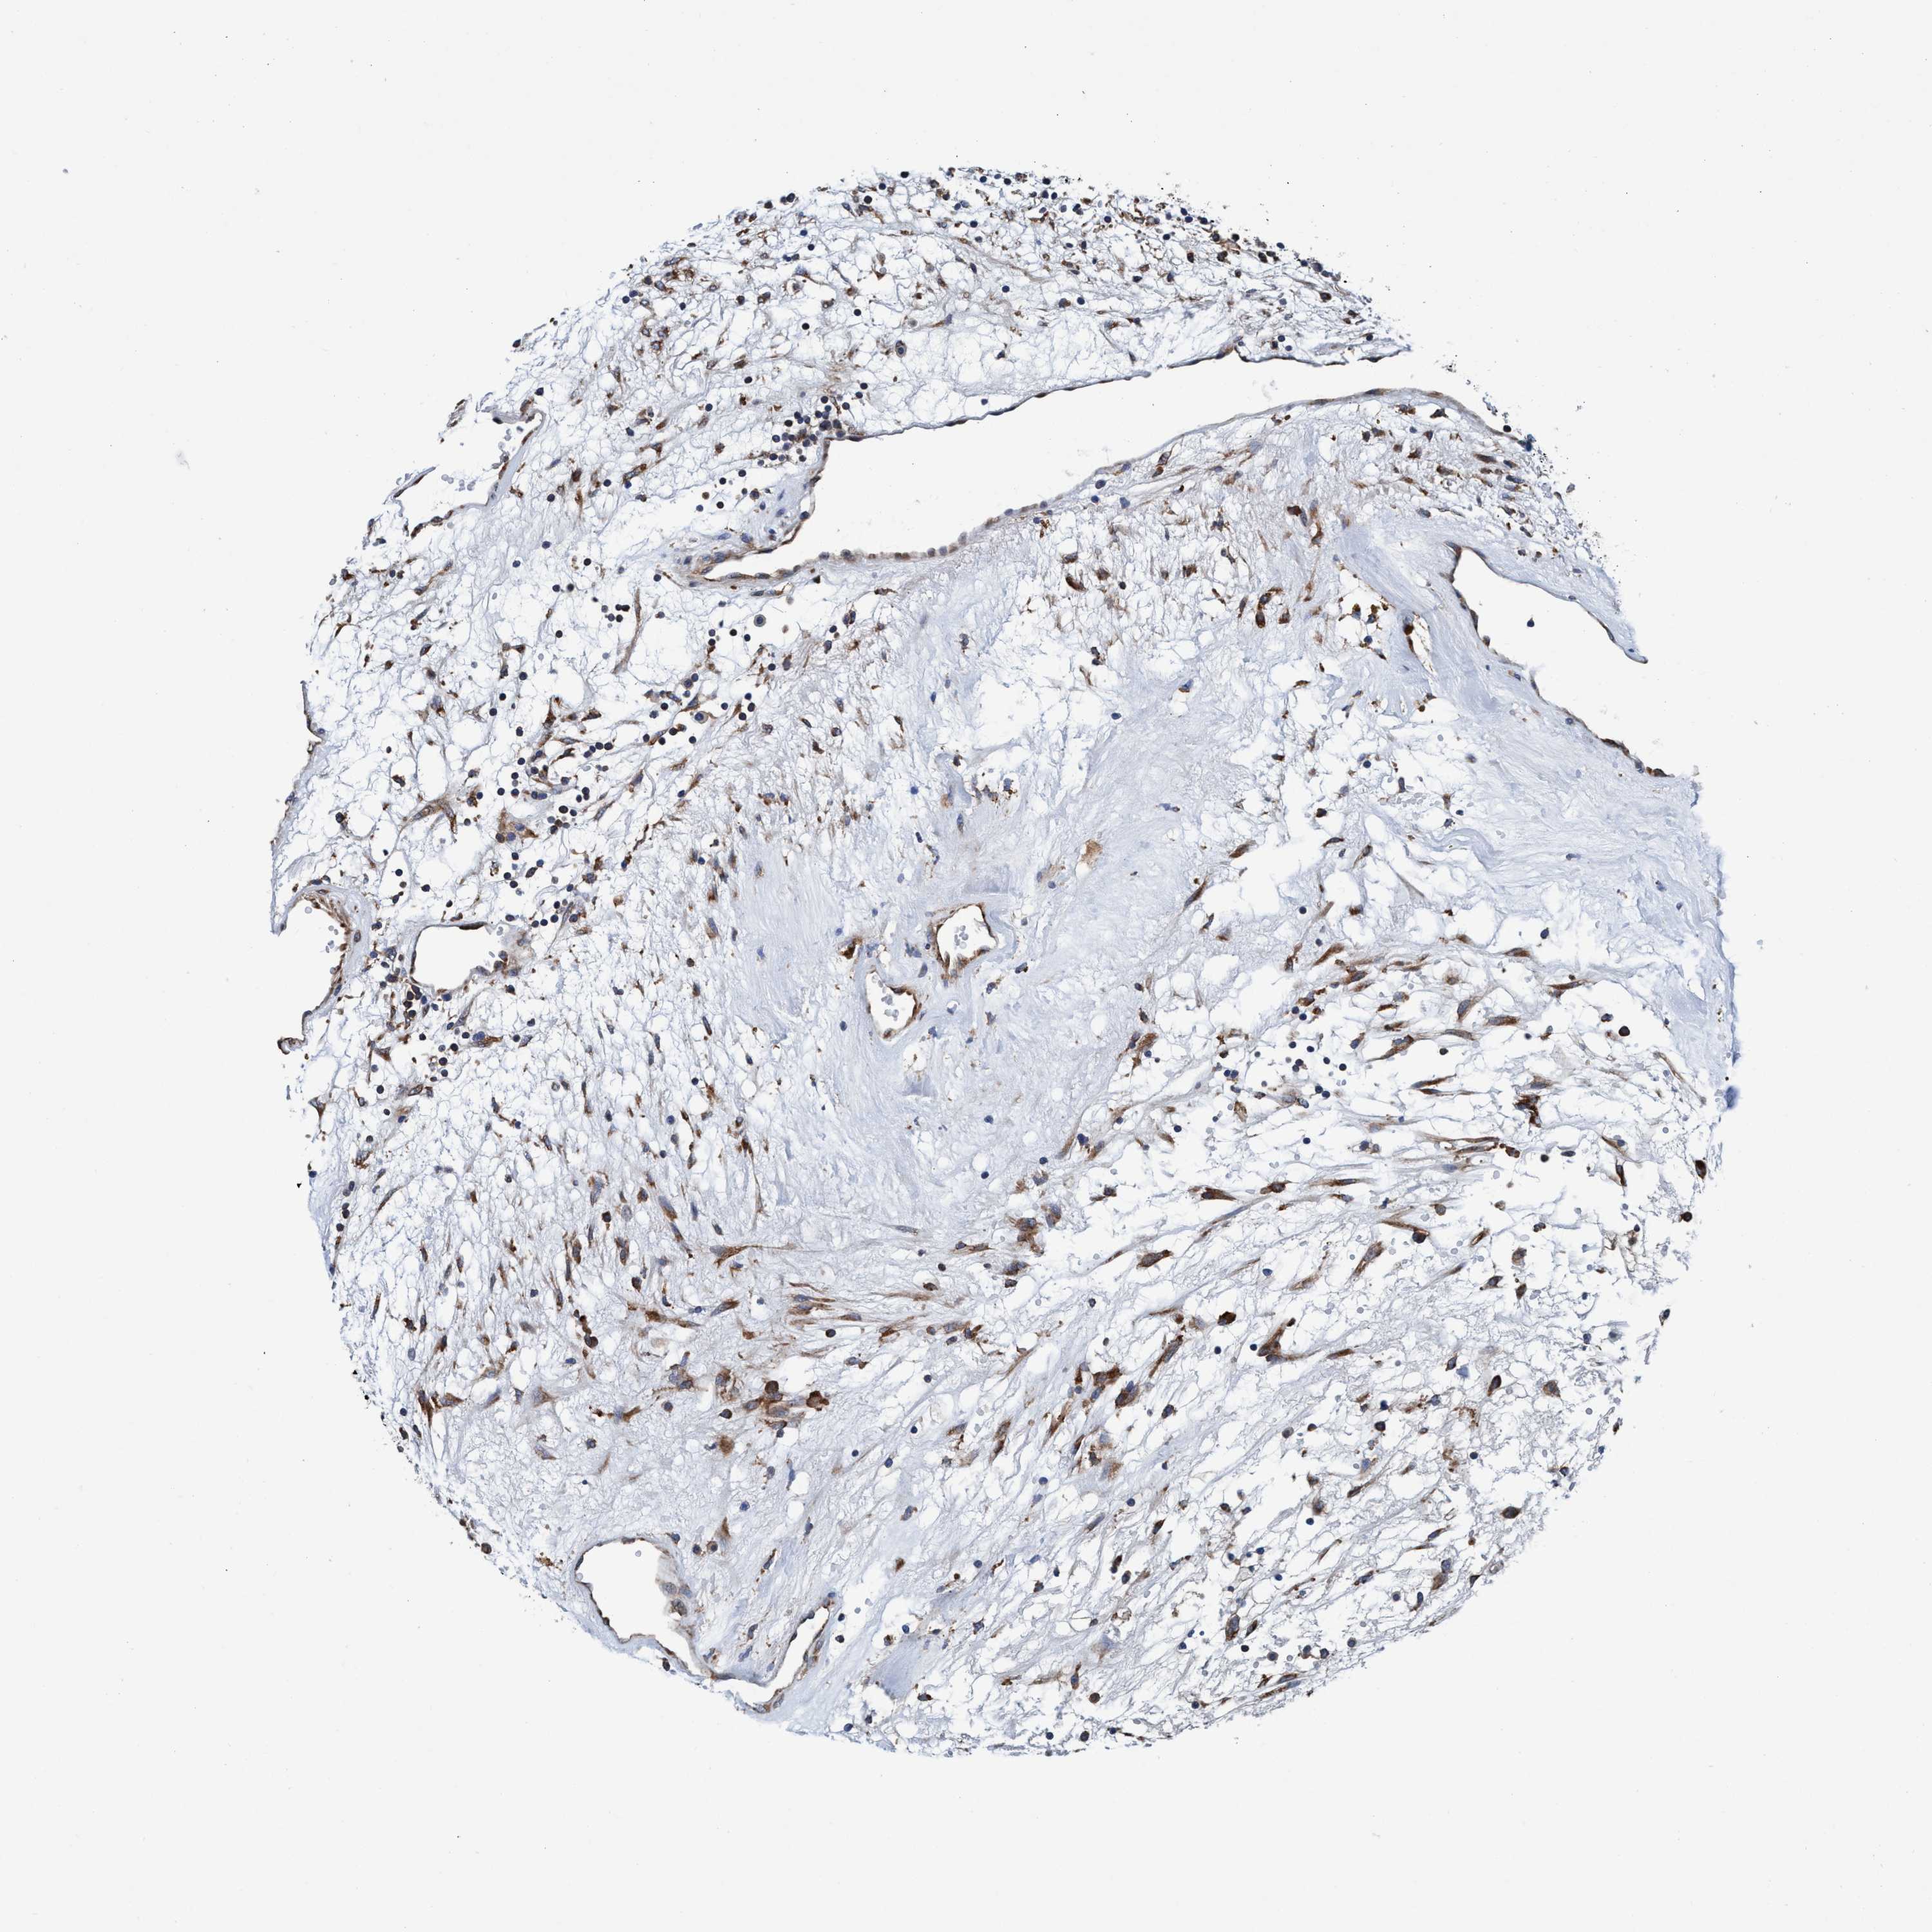

KIDNEY RENAL CLEAR CELL CARCINOMA (VALIDATION) - Interactive survival scatter ploti

The Survival Scatter plot shows the clinical status (i.e. dead or alive) for all individuals in the patient cohort, based on the same data that underlies the corresponding Kaplan-Meier plots. Patients that are alive at last time for follow-up are shown in blue and patients who have died during the study are shown in red.

The x-axis shows the expression levels (FPKM) of the investigated gene in the tumor tissue at the time of diagnosis. The y-axis shows the follow-up time after diagnosis (years). Both axes are complimented with kernel density curves demonstrating the data density over the axes. The top density plot shows the expression levels (FPKM) distribution among dead (red) and alive patients (blue). The right density plot shows the data density of the survived years of dead patients with high and low expression levels respectively, stratified using the cutoff indicated by the vertical dashed line through the Survival Scatter plot. This cutoff is automatically defined based on the FPKM cutoff that minimizes the p-score. The cutoff can be changed by dragging the vertical line or by entering a cutoff value in the square labeled "Current cut-off".

Under the Survival Scatter plot the p-score landscape (black curve; left axis) is shown together with dead median separation (red curve; right axis). Dead median separation is the difference in median mRNA expression between patients who have died with high and low expression, respectively. It is calculated as follows: median FPKM expression of dead patients with high expression - median FPKM expression of dead patients with low expression. This is intended to aid the user in visually exploring custom cutoffs and the associated p-scores and dead median separation.

Individual patient data is displayed and can be filtered by clicking on one or more of the category buttons on the top of the page. Categories describing expression level and patient information include: high, low, alive, dead, female, male and tumor stages. The scale of the x-axis can be toggled between linear and log-scale by clicking on the "x log" button. Mouse-over function shows TCGA ID, patient information and mRNA expression (FPKM) for each patient.

& Survival analysisi

Kaplan-Meier plots summarize results from analysis of correlation between mRNA expression level and patient survival. Patients were divided based on level of expression into one of the two groups "low" (under cut off) or "high" (over cut off). X-axis shows time for survival (years) and y-axis shows the probability of survival, where 1.0 corresponds to 100 percent.

ENDOG is not prognostic in Kidney Renal Clear Cell Carcinoma (validation)

Best expression cut offi

Based on the FPKM value of each gene, patients were classified into two groups and association between prognosis (survival) and gene expression (FPKM) was examined. The best expression cut-off refers the FPKM value that yields maximal difference with regard to survival between the two groups at the lowest log-rank P-value. Best expression cut-off was selected based on survival analysis .

When clicking on this number, the vertical dashed line indicating cut-off, the interactive survival plot, and the Kaplan-Meier curve will be adjusted to show results based on the best expression cut-off.

: 20.69

TCGA RNA samplesi

RNA-seq data is reported as average FPKM (number Fragments Per Kilobase of exon per Million reads), generated by the The Cancer Genome Atlas (TCGA) .

Normal distribution across the dataset is visualized with box plots, shown as median and 25th and 75th percentiles. Points are displayed as outliers if they are above or below 1.5 times the interquartile range. FPKM values of the individual samples are presented next to the box plot.

Average pTPM 14.7

Number of samples 100